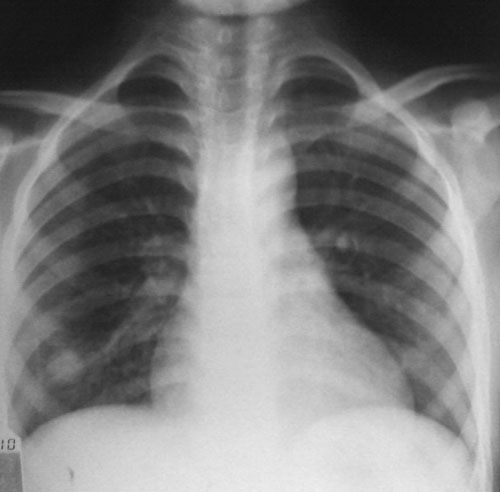

标题: PED2980:男、12岁、轻咳伴发热。

右肺结节灶,左肺好像也有,建议ct明确。

右肺下野圆形结节,考虑血源性肺脓肿,肺炎不除外

球形病灶,临床有感染症状,血源性肺脓肿不排除。tb及支原体肺炎不会出现此征象。

球形病灶,临床有感染症状,血源性肺脓肿不排除。肺血管畸形要排除

这样的结节,没有什么特异的征象。不做ct,就是猜。可能性很多,但都不准确。